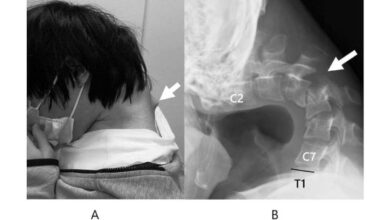

Joven en Japón desarrolló síndrome de la cabeza caída: Esta sería la razón

Un joven japonés de 25 años desarrolló el síndrome de cabeza caída tras años de uso excesivo de su teléfono…

Un joven japonés de 25 años desarrolló el síndrome de cabeza caída tras años de uso excesivo de su teléfono…